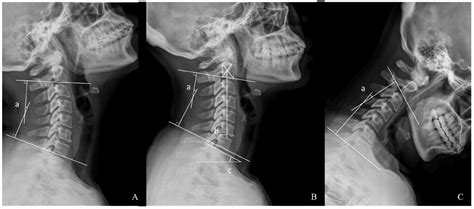

Sex X Ray technology involves the use of X-rays to produce images of the internal structures of the reproductive and sexual organs. This type of imaging is particularly useful for diagnosing conditions that affect the reproductive system, such as tumors, infections, and anatomical abnormalities. The technology works by passing X-rays through the body, which are then captured on a detector to create detailed images.

- Pelvic X-Ray: A general X-ray of the pelvic region that can help identify fractures, tumors, or other abnormalities in the bones and soft tissues.